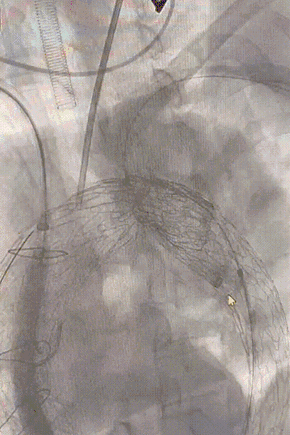

经股动脉真腔置入金标猪尾导管进行主动脉弓部造影。右侧股动脉沿加硬导丝置入24Fr DSF导引鞘后,右侧股动脉及左侧肱动脉之间V18导丝建立牵张通路。

gore医疗怎么样「胸有乾坤」强弓硬弩 一蹴而就——CTAG弓上三开窗治疗主动脉夹层病例报道_https://www.jmylbn.com_新闻资讯_第8张

主动脉弓造影